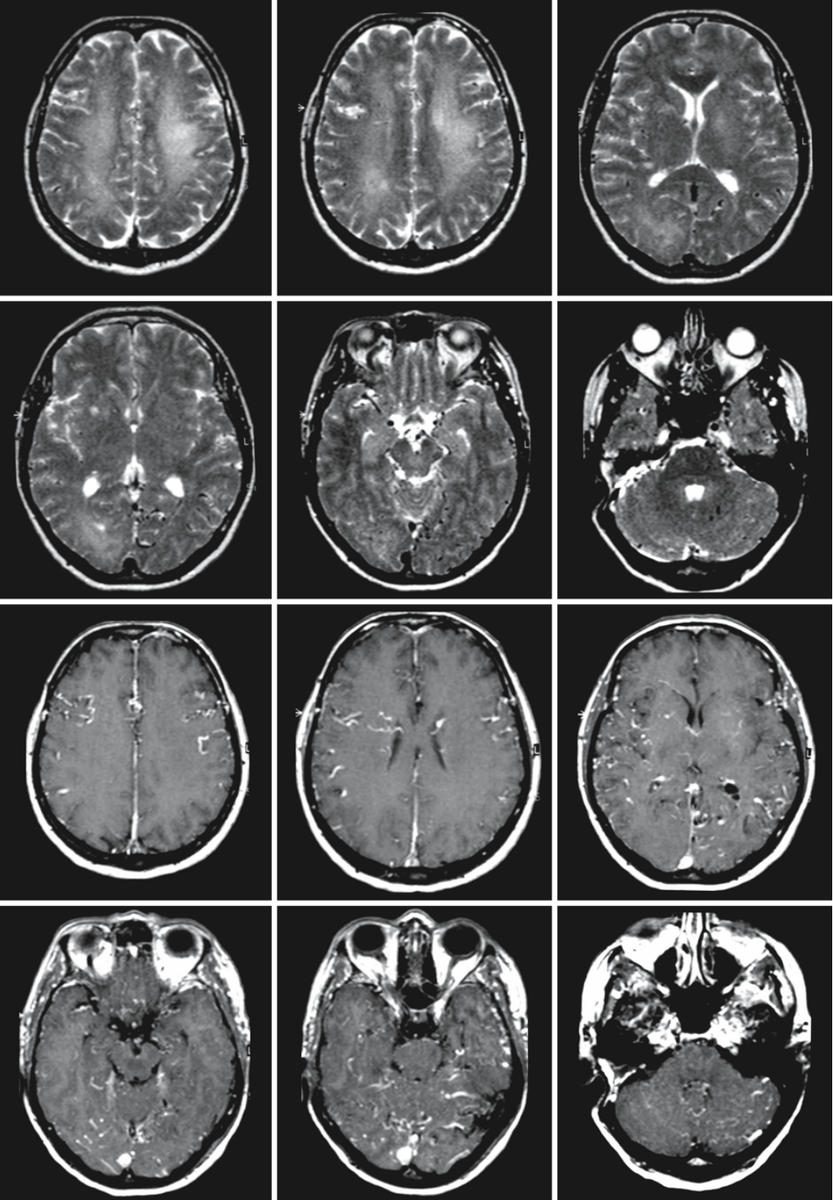

67-летняя женщина в анамнезе перенесла операцию по удалению акустической невриномы справа. Она обратилась с жалобами на быстрое снижение когнитивных функций. На Т2-взвешенных изображениях (первые два ряда) наблюдается диффузное повышение сигнала в глубоких слоях белого вещества обоих полушарий мозга. Аномальные "пустоты потока" заметны на поверхности мозга и в его паренхиме, особенно в височных долях и в задней черепной ямке. Т1-взвешенные изображения с контрастированием (третий и четвертый ряды) демонстрируют обширное усиление корковых и паренхиматозных вен.